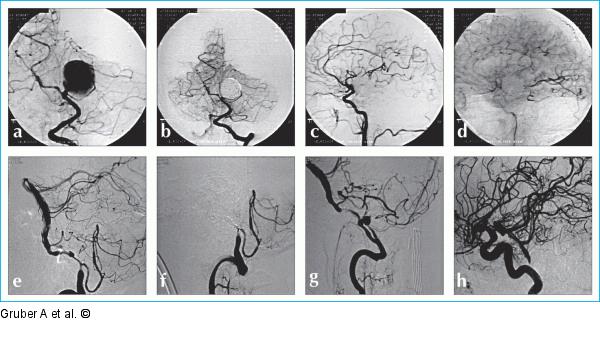

Abbildung 12a-h: "Flow modification"-Technik "Flow modification"-Technik durch sogenanntes "Flow reversal". Fall 1 (a–d): Breitbasiges Riesenaneurysma der Arteria cerebri posterior links distal des Abganges der perforierenden Äste (a). Nach Ballontestokklusion wird das Aneurysma unter Verschluß der linken A. cerebri posterior mit absetzbaren Platin-Coils verschlossen (b). Die A. cerebri posterior distal des Aneurysmas füllt sich retrograd über Kollateralkreisläufe aus dem Stromgebiet der A. carotis interna links (c–d). Fall 2 (e–h): Subarachnoidalblutung bei beidseitiger spontaner Dissektion der Vertebralarterien und unklarer Blutungsquelle. Nach PAO der rechten Arteria vertebralis distal des Abgangs der A. cerebelli inferior posterior (e–f) wird die linke Vertebralarterie (g) nach Ballontestokklusion und dokumentierter Flußumkehr in der A. basilaris (h) durch guten beidseitigen Cross flow über die Aa. communicantes posteriores ebenfalls ohne ischämische Komplikation verschlossen. |

"Flow modification"-Technik durch sogenanntes "Flow reversal". Fall 1 (a–d): Breitbasiges Riesenaneurysma der Arteria cerebri posterior links distal des Abganges der perforierenden Äste (a). Nach Ballontestokklusion wird das Aneurysma unter Verschluß der linken A. cerebri posterior mit absetzbaren Platin-Coils verschlossen (b). Die A. cerebri posterior distal des Aneurysmas füllt sich retrograd über Kollateralkreisläufe aus dem Stromgebiet der A. carotis interna links (c–d). Fall 2 (e–h): Subarachnoidalblutung bei beidseitiger spontaner Dissektion der Vertebralarterien und unklarer Blutungsquelle. Nach PAO der rechten Arteria vertebralis distal des Abgangs der A. cerebelli inferior posterior (e–f) wird die linke Vertebralarterie (g) nach Ballontestokklusion und dokumentierter Flußumkehr in der A. basilaris (h) durch guten beidseitigen Cross flow über die Aa. communicantes posteriores ebenfalls ohne ischämische Komplikation verschlossen. |